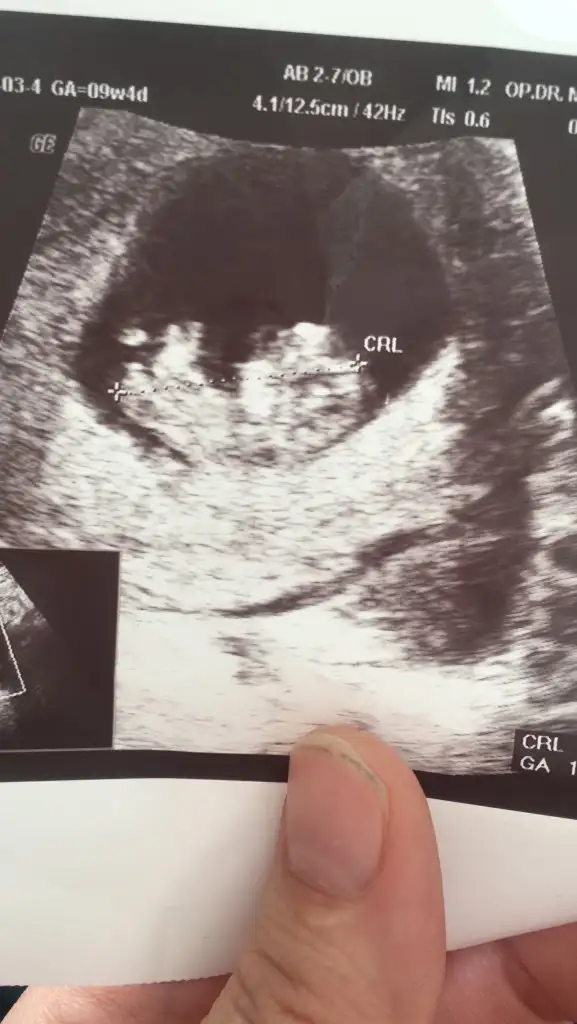

Bir arkadaşın bebeği varmı bir tahmininiz 12 haftalık

Acısı 30° canım belkide ileri haftada yükselir başka USG varsa paylaşın 11+4 USG erkekte olabilir 🤗13 haftada nubu tam net olur aslında 🙈 oranları ilk sayfaya yazmıştım